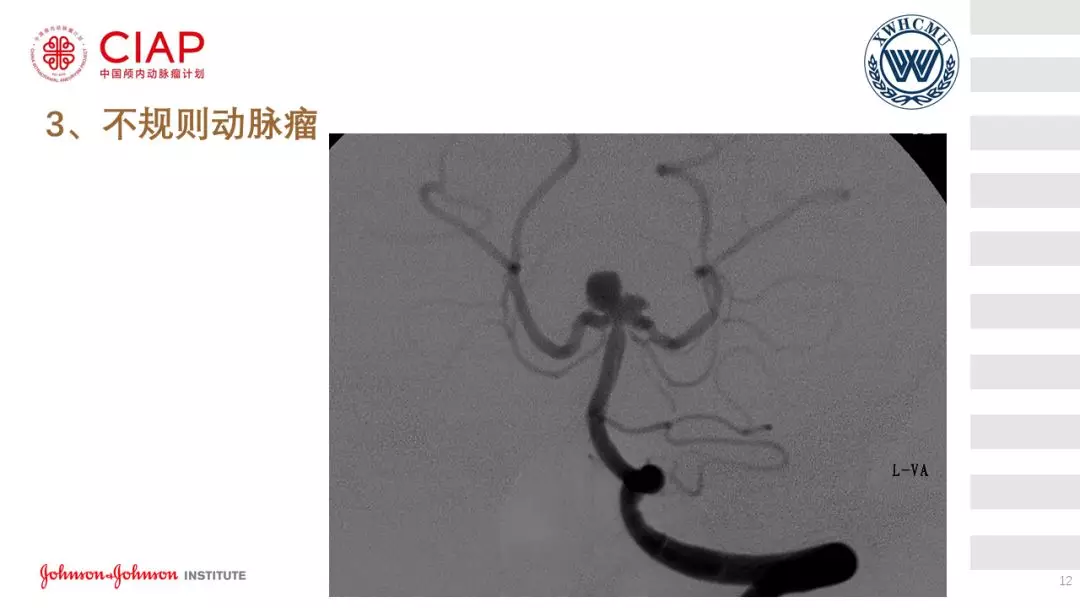

张鹏教授:不同辅助方法下栓塞动脉瘤弹簧圈的选择